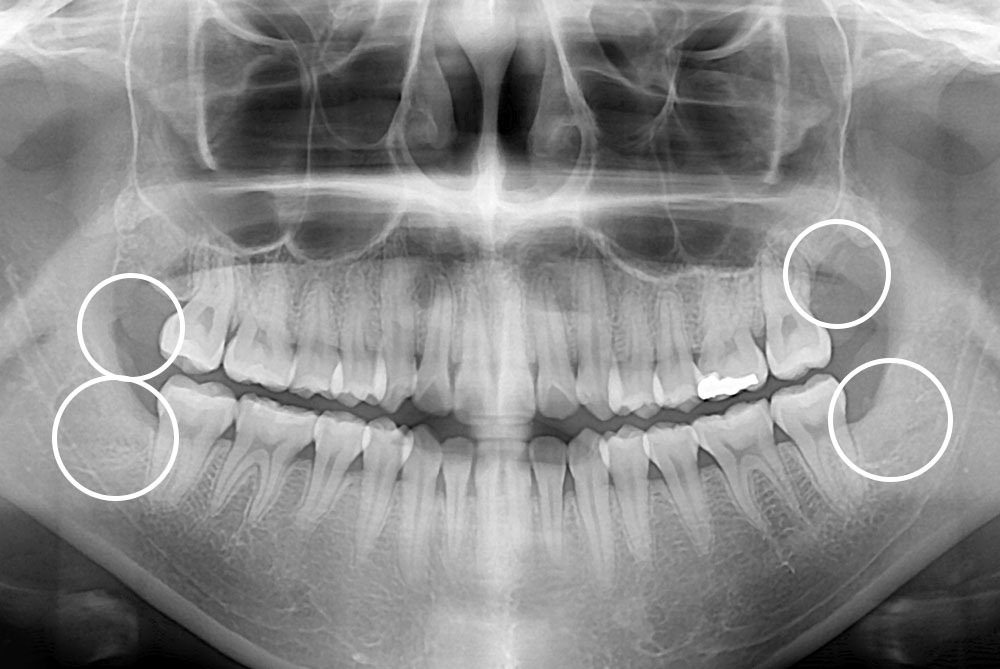

[사랑니] 매복 사랑니 발치

치료전 : 2019-08-05